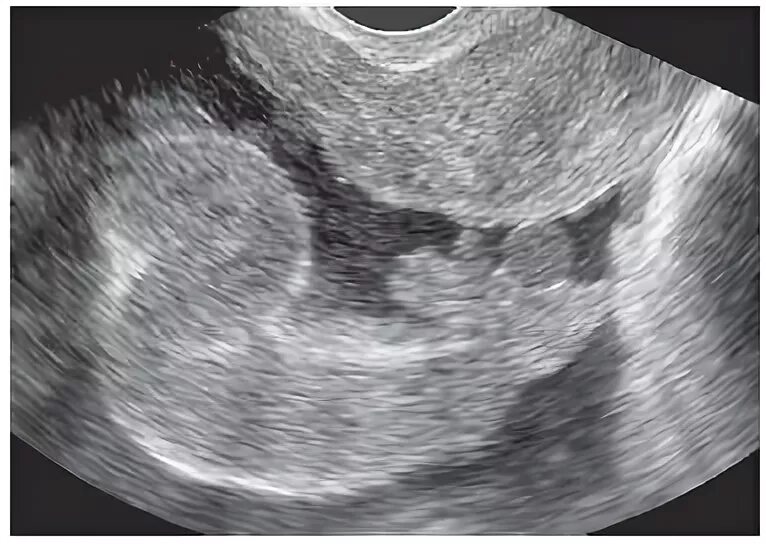

Pyosalpinx латынь